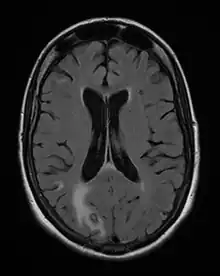

Acute toxoplasmosis is often asymptomatic in healthy adults.[13][14] However, symptoms may manifest and are often influenza-like: swollen lymph nodes, headaches, fever, and fatigue,[15] or muscle aches and pains that last for a month or more. It is rare for a human with a fully functioning immune system to develop severe symptoms following infection. People with weakened immune systems are likely to experience headache, confusion, poor coordination, seizures, lung problems that may resemble tuberculosis or Pneumocystis jiroveci pneumonia (a common opportunistic infection that occurs in people with AIDS), or chorioretinitis caused by severe inflammation of the retina (ocular toxoplasmosis).[15] Young children and immunocompromised people, such as those with HIV/AIDS, those taking certain types of chemotherapy, or those who have recently received an organ transplant, may develop severe toxoplasmosis. This can cause damage to the brain (encephalitis) or the eyes (necrotizing retinochoroiditis).[16] Infants infected via placental transmission may be born with either of these problems, or with nasal malformations, although these complications are rare in newborns. The toxoplasmic trophozoites causing acute toxoplasmosis are referred to as tachyzoites, and are typically found in various tissues and body fluids, but rarely in blood or cerebrospinal fluid.[17]

Due to the absence of obvious symptoms,[13][14] hosts easily become infected with T. gondii and develop toxoplasmosis without knowing it. Although mild, flu-like symptoms occasionally occur during the first few weeks following exposure, infection with T. gondii produces no readily observable symptoms in healthy human adults.[7][20] In most immunocompetent people, the infection enters a latent phase, during which only bradyzoites (in tissue cysts) are present;[21] these tissue cysts and even lesions can occur in the retinas, alveolar lining of the lungs (where an acute infection may mimic a Pneumocystis jirovecii infection), heart, skeletal muscle, and the central nervous system (CNS), including the brain.[22] Cysts form in the CNS (brain tissue) upon infection with T. gondii and persist for the lifetime of the host.[23] Most infants who are infected while in the womb have no symptoms at birth, but may develop symptoms later in life.[24]

Diagnosis of toxoplasmosis in humans is made by biological, serological, histological, or molecular methods, or by some combination of the above.[60] Toxoplasmosis can be difficult to distinguish from primary central nervous system lymphoma. It mimics several other infectious diseases so clinical signs are non-specific and are not sufficiently characteristic for a definite diagnosis. As a result, the possibility of an alternative diagnosis is supported by a failed trial of antimicrobial therapy (pyrimethamine, sulfadiazine, and folinic acid (USAN: leucovorin)), i.e., if the drugs produce no effect clinically and no improvement on repeat imaging.

- Nawaz Khan, A (2015). "Imaging in CNS Toxoplasmosis". Medscape Web Site.

The seroprevalence of T. gondii in humans varies between 10 and 70% worldwide, depending on the region and increases significantly with age. Upon infection, the parasites persist as intraneuronal cysts in the central nervous system (CNS) for the lifetime of the host (1, Figure 1). Until recently, parasite persistence in healthy individuals was regarded as clinically asymptomatic. However, in the last decade, several reports have indicated that chronic cerebral toxoplasmosis may impact on the behaviour of its host (2).